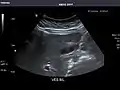

Aorta

Aorta: Visualized portions normal in caliber, 16 x 15 mm.